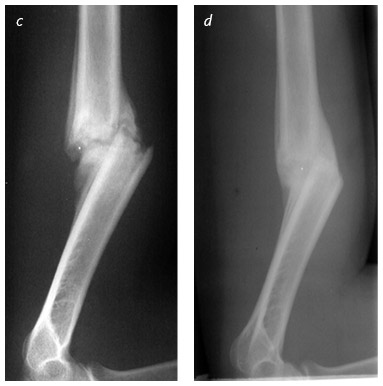

Вид сбоку показывает этапы заживления и перестройки кости при переломе плеча: на момент повреждения (a), через четыре недели (b), через восемь недель (c) и через шестнадцать недель (d), когда перелом хорошо зажил. Остеокласты притупляют острые углы, а остеобласты наслаивают новую костную ткань, стабилизируя перелом. Вместе эти строители и разрушители постепенно восстанавливают правильное расположение и форму кости